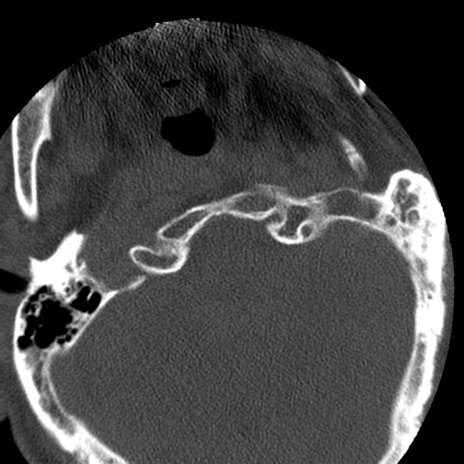

症例50 頚椎CT(横断像)

冠状断像